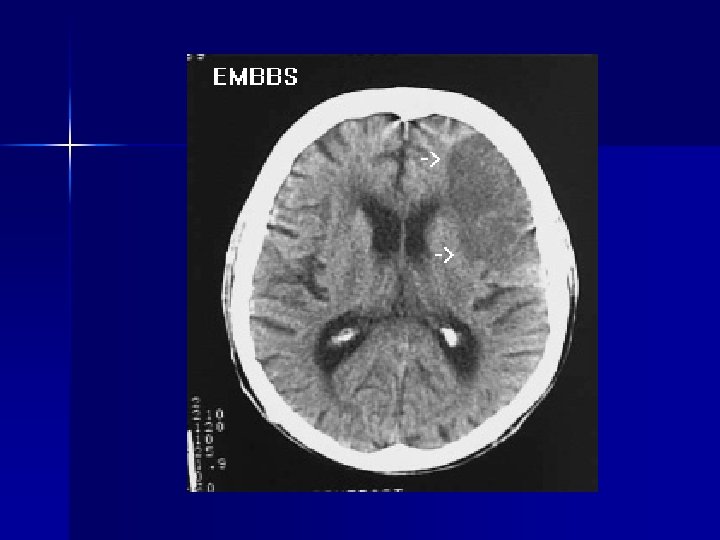

n n Tumor: 70% with headache, classically worse in the morning, positional, nausea and vomiting Pseudotumor cerebri: headache worse with awakening, valsalva, cough, bending – Signs of increased ICP: papilledema, CN VI palsy, diploia, visual deficits, tinnitus – Linked with OCP use, vit A, tetracycline use, thyroid disorders – Diagnosed with CT for hydrocephalus, LP for high opening pressure – Treatment diuretics, repeat LP, CSF shunt or optic nerve sheath fenestration